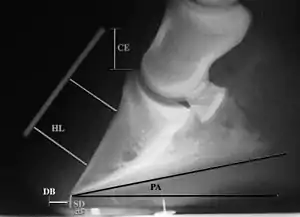

Radiographs

Several radiographic measurements, made on the lateral view, allow for objective evaluation of the episode.

- Coronary extensor distance (CE): the vertical distance from the level of the proximal coronary band to the extensor process of P3. It is often used to compare progression of the disease over time, rather than as a stand-alone value. A rapidly increasing CE value can indicate distal displacement (sinking) of the coffin bone, while a more gradual increase in CE can occur with foot collapse. Normal values range from 0–30 mm, with most horses >12–15 mm.[1]

- Sole depth (SD): the distance from the tip of P3 to the ground.

- Digital breakover (DB): distance from the tip of P3 to the breakover of the hoof (dorsal toe).[1]

- Palmar angle (PA): the angle between a line perpendicular to the ground, and a line at the angle of the palmar surface of P3.

- Horn:lamellar distance (HL): the measurement from the most superficial aspect of the dorsal hoof wall to the face of P3. 2 distances are compared: a proximal measurement made just distal to the extensor process of P3, and a distal measurement made toward the tip of P3. These two values should be similar. In cases of rotation, the distal measurement will be higher than the proximal. In cases of distal displacement, both values will increase, but may remain equal. Therefore, it is ideal to have baseline radiographs for horses, especially for those at high-risk for laminitis, to compare to should laminitis ever be suspected. Normal HL values vary by breed and age:[1]